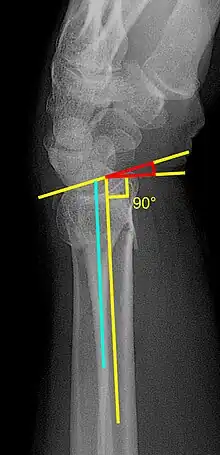

Various kinds of information can be obtained from X-rays of the wrist:[5]

Lateral view

- Volar or dorsal tilt - A line is drawn joining the most distal ends of the volar and dorsal side of the radius. Another line perpendicular to the longitudinal axis of the radius is drawn. The angle between the two lines is the angle of volar or dorsal tilt of the wrist. Measurement of volar or dorsal tilt should be made in true lateral view of the wrist because pronation of the forearm reduces the volar tilt and supination increases it. When dorsal tilt is more than 11 degrees, it is associated with loss of grip strength and loss of wrist flexion.[5]

Posteroanterior view

- Radial inclination - It is the angle between a line drawn from the radial styloid to the medial end of the articular surface of the radius and a line drawn perpendicular to the long axis of the radius. Loss of radial inclination is associated with loss of grip strength.[5]

- Radial length - It is the vertical distance in millimetres between a line tangential to the articular surface of the ulna and a tangential line drawn at the most distal point of radius (radial styloid). Shortening of radial length more than 4mm is associated with wrist pain.[5]

- Ulnar variance - It is the vertical distance between a horizontal line parallel to the articular surface of the radius and another horizontal line drawn parallel to the articular surface of the ulnar head. Positive ulnar variance (ulna appears longer than radius) disturbs the integrity of triangular fibrocartilage complex and is associated with loss of grip strength and wrist pain.[5]